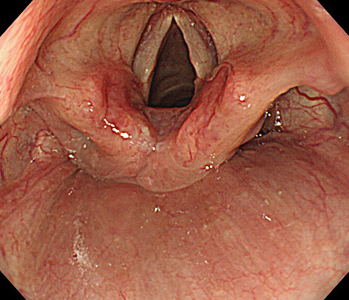

胃内視鏡(胃カメラ)画像

| ◆ 経口内視鏡(高解像度)◆ | ◆ 経鼻内視鏡 ◆ |

| 喉頭 | 喉頭(経鼻) |